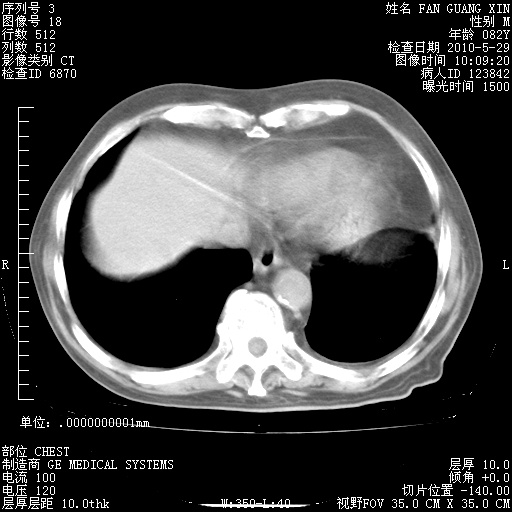

治疗3周后的肺部CT纵隔窗

再治疗10天后的肺部CT

再治疗10天后的肺部CT 纵膈窗

阅读此次胸部CT,肺间质渗出性改变较入院时有吸收。目前从体温、白细胞、中性分叶明显增高,肯定存在细菌感染(发生医院感染哦,若无消化道及泌尿系统等感染的依据,肺部感染可能大)。若你院头孢哌酮舒巴坦钠耐药率较高,同意你的方案,若48小时体温仍高,可考虑使用碳青霉稀类抗菌药物,同时可予超声雾化、注意滴数时加大液体量。白蛋白33.30g/L较低哦,需加强营养等支持治疗。